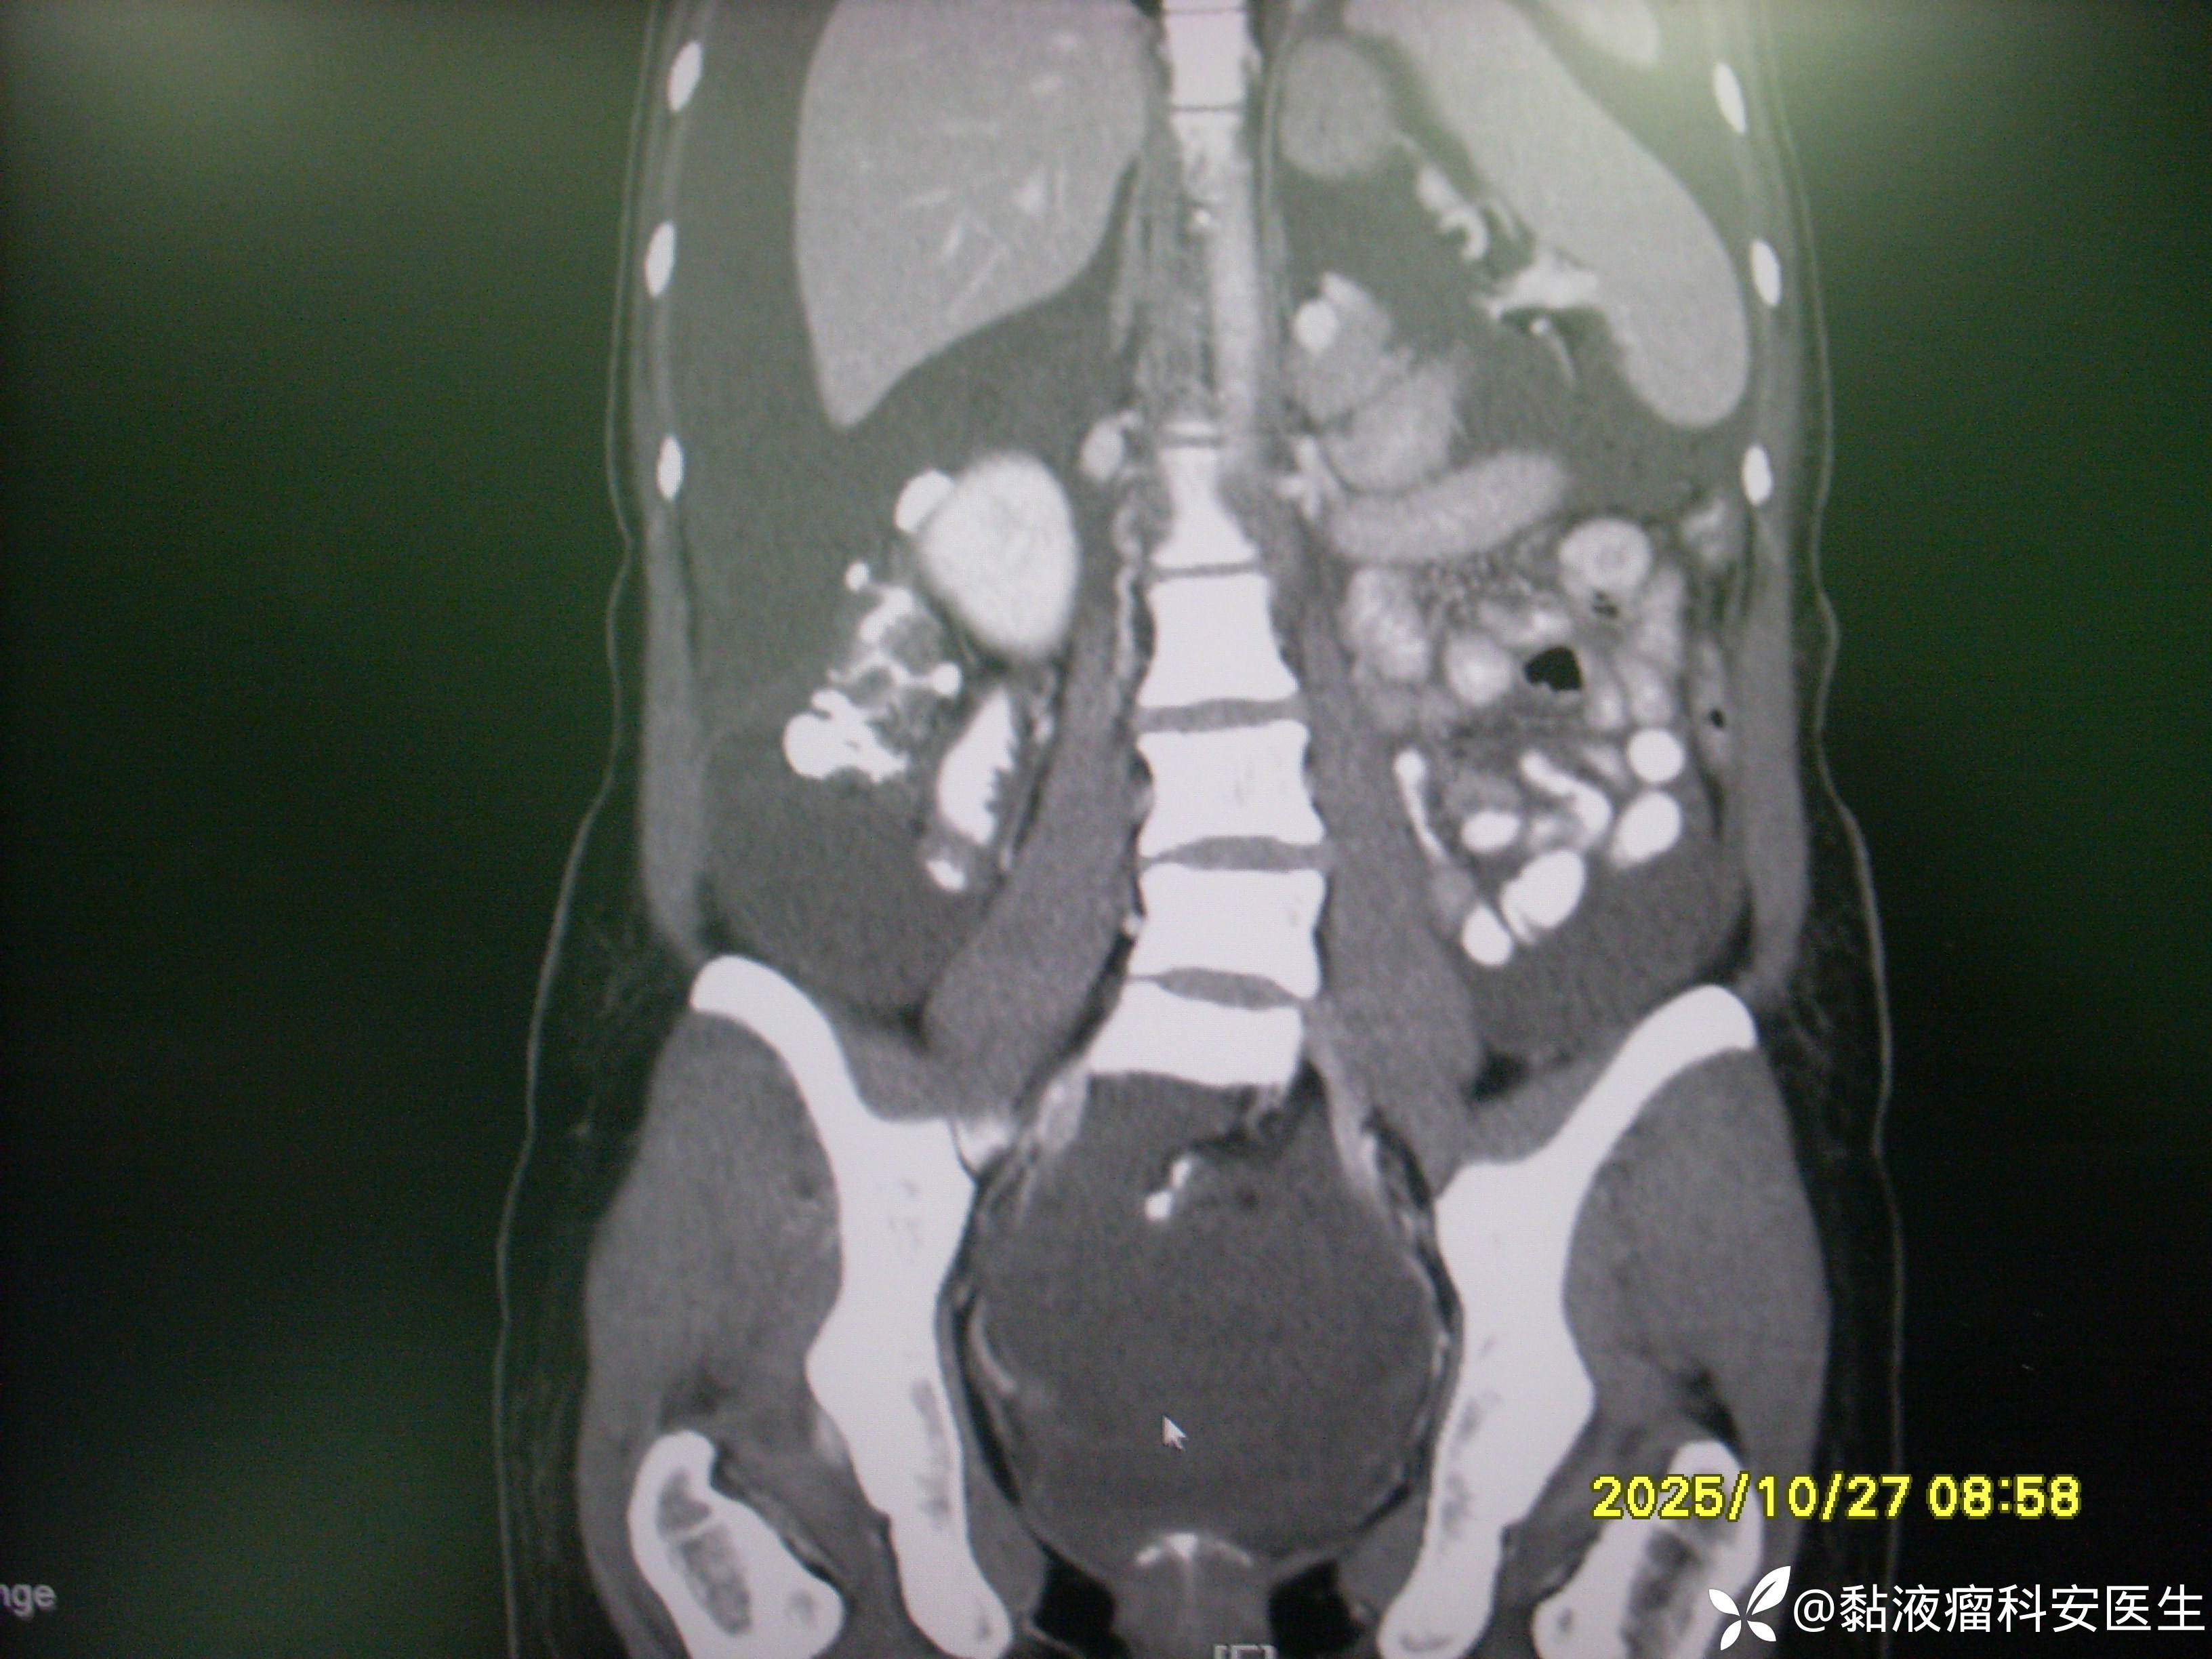

术前CT

腹腔巨大占位是什么?